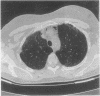

A pneumomediastinum occurred after a transbronchial biopsy in a woman with pulmonary fibrosis and was confirmed by computed tomography. Although pneumomediastinum has a pathogenesis similar to that of pneumothorax it has not been reported after transbronchial biopsy.